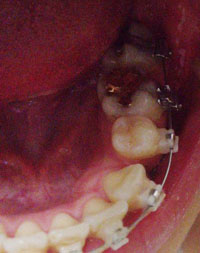

드디어 하악 제일 안쪽 어금니에 교정장치 부착했어요.

그동안 왼쪽 오른쪽 제일 안쪽 어금니에는 교정장치를 부착하지 않은 상태였는데요~

이번에 오른쪽에만 교정장치를 부착하고,

왼쪽 어금니는 교합상태 등 치아 상태를 보고 차후에 교정장치를 부착하기로 했어요.

그리고, 상악에 발치공간을 좀 더 늘리기 위해서~

지난 월치료때와 동일하게 스프링을 조절했어요.

왼쪽에는 발치공간 자리가 많이 확보가 되었는데

오른쪽에 발치공간 자리가 조금 더 필요하다고 하시면서

조금 더 늘리자고 하시면서 스프링을 교체하고 쪼이는? 조절을 해주셨어요.

발치공간을 넓히는 이유는 돌출된 앞니를 완벽하게 밀어 넣기 위해서인데요~

저의 경우 치아를 교정발치한 공간만으로는 완벽하게 돌출입 해소가 어려울꺼 같아

스프링을 부착, 연결해서 제일 안쪽 어금니를 뒤로 밀어 넣으면서 공간을 확보하는거에요.